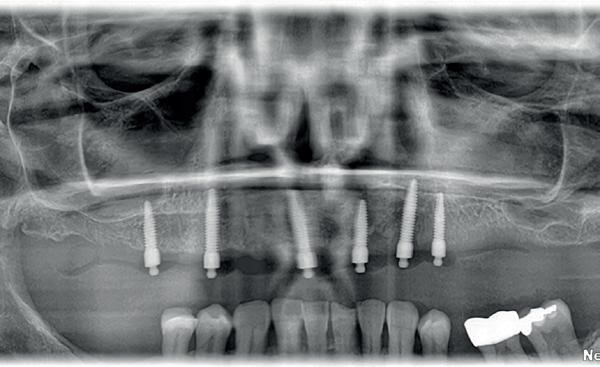

Voor het implantologisch onderzoek werd een CBCTscan (Trium CBCT, Acteon Frankrijk) vervaardigd van de edentate bovenkaak en in de software werd een planning gemaakt van 6 implantaten in de bovenkaak. De kaak kan opgedeeld worden in het front, tussen de 13 en 23 en de zijdelingse delen van de 14 t/m 17 en 24 t/m 27. Er dienen 2 implantaten in het front geplaatst te worden en 2 implantaten in de zijdelingse delen rechts en links, om een optimale verdeling van de implantaten (implant spread) te krijgen. De implantaten in deze casus werden gepland op posities 12, 22, 14, 24, 16 en 27. Tevens werd rekening gehouden met de krachtenverdeling óp de implantaten, deze zijn naar dorsaal toe forser dan in het front, daarom werd er gekozen voor brede implantaten (meer dan 5.0 mm in diameter) distaal en 4.0 mm diameter implantaten in het front. Voor de 16 was een crestale sinusbodemelevatie nodig en de 14 benodigde een kaakverbreding en verhoging.

Om de implantaten op de juiste vooraf geplande positie te implanteren, zijn er een aantal mogelijkheden (afbeelding 1 en 2). Eén daarvan is om de chirurgie guided uit te voeren, maar dat is lastig omdat de guide niet op elementen afgesteund kan worden. De guide dient dan met guide pins vastgeschroefd te worden, maar dat heeft als nadeel dat bij verplaatsing van de guide de implantaten niet op de juiste positie staan. Bij immediaat implanteren kan tegenwoordig gebruikgemaakt worden van meerdere stac-

kable guides, die op een base guide geklikt kunnen worden. Een tweede methode is om op basis van de CBCT-scan in de mond uit te meten waar de implantaat locaties zijn en door te kijken naar referentie van de onderkaak. In deze cases werd besloten om de implantaten vrij uit de hand te plaatsen.

Chirurgie plaatsen van de 6 implantaten

Voor de behandeling kreeg de patiënt Amoxicilline 500mg 3dd1 gedurende een week voorgeschreven waarbij er een dag voor de chirurgie gestart werd, als pijnstilling Ibuprofen 600 mg 3dd1 voor een week en Blue M Mouthwash voor de mondspoeling gedurende de eerste 2 weken. Na de anesthesie werd een incisie gemaakt van tuber tot tuber en werd de

voor de implantaten (afbeelding 3). Hierna werd met een meetinstrument de locaties van de implantaten uitgemeten en werd een initiële osteotomie op deze locaties gemaakt. Voor de 16 werd een crestale sinusbodemelevatie met Densah boren uitgevoerd. Hierbij werd het zachte bot gecondenseerd om naar crestaal geduwd te worden, waarna het membraan van Schneider meelifte. Door de osteotomie werden 1cc botkorrels geplaatst en daarna direct het implantaat. Ter plaatse van de 14 zat een verticaal botdefect, na plaatsen van dit implantaat, werd de kaak verticaal verhoogd. Er werden 6 implantaten van het merk AnyRidge (MegaGen Implant Company, Korea) geplaatst met diameter 5.0 mm aan de distale zijdes, diameter 4.5 mm bij de premolaren en 4.0 mm implantaten bij de laterale incisieven (afbeelding 4).

Ter plaatste van de 16 en 14 werden verticale matrashechtingen geplaatst, waarna er één doorlopende hechtingen van tuber tot tuber volgde met een 4-0 gevlochten hechtdraad (afbeelding 5). Gedurende de eerste 2 weken van de genezing is het van essentieel belang voor de wondgenezing, dat de patient geen bovenprothese draagt. Deze werd daarom ingenomen, met de uitleg dat direct dragen van de bovenprothese een nadelige invloed heeft op de genezing van de kaak, de botopbouw en de implantaten. Patiënt kwam 2 weken na de chirurgie retour voor het verwijderen van de hechtingen, waarna de binnenzijde van de bovenprothese werd uitgeslepen en voorzien werd van een softliner als nieuwe tijdelijke voering voor retentie van de bovenprothese. Vanwege de kaakverhoging en sinusbodemelevatie, werd 6 maanden genezing afgewacht van het bot en integratie van de implantaten.

Tweede fase chirurgie

Na de genezingsperiode werd eerst een OPT röntgenopname vervaardigd om de genezing van de implantaten, kaakverbreding en sinusbodemelevatie te beoordelen. Er waren geen complicaties opgetreden. Bij de tweede fase chirurgie is het van absoluut belang dat er minimaal 2-3 mm gekeratiniseerd weefsel aan de buccale zijde van de implantaten wordt verkregen, anders kan de patiënt de implantaten niet goed reinigen en door de trekkrachten van de mucosa ontstaat al gauw peri-implantaire ontstekingen en recessies. De incisie hoeft niet van tuber tot tuber te zijn, maar 2 incisies van de 16 tot de 12 en 26 tot de 22 is voldoende, waarbij de incisie genoeg gekeratiniseerd weefsel aan de buccale zijde bevat, dat naar